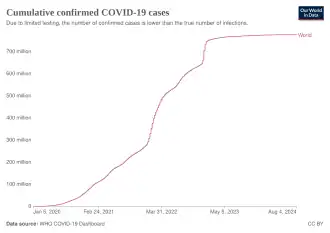

| Frequency | 778,384,946[4] confirmed cases (true case count is expected to be much higher[5]) |

-

Total confirmed cases over time

Total confirmed cases over time -